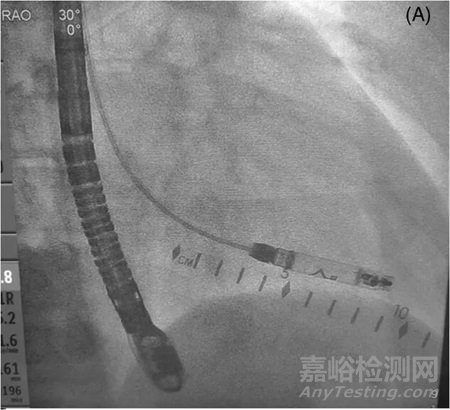

圖1 心室無(wú)導(dǎo)聯(lián)展開(kāi)前的右前斜肌